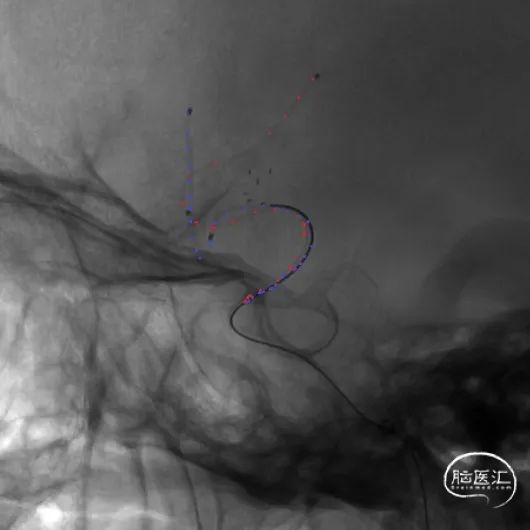

经下干的SL-10微导管释放第二枚Atlas支架,形成“Y”型支架形态,充分保护上下两干,Atlas支架打开顺畅,影像下可清晰看到两端标记点完全打开。第二枚支架释放完毕后,顺势将该SL-10微导管经支架网眼顺利超选入瘤腔,拟双微管填塞。经一根SL-10微导管释放第一枚Target XL 4mm*12cm弹簧圈进行成篮。

相继填入Target系列弹簧圈,型号分别为2mm*8cm、2mm*6cm(两枚)、1.5mm*4cm(两枚)。